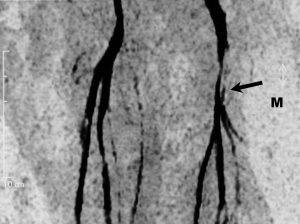

Магнитно-резонансная ангиография сосудов ног у мужчины 67 лет. Жалуется на медленно растущую массу на левой ноге. На изображении видно медиальное смещение и сдавление левой бедренной артерии, поверхностной бедренной артерии. Данная опухоль привела к хромоте.

Ангиография

Липосаркомы обычно гиповаскулярные, они вытесняют крупные сосуды, в частности нижнюю полую вену. В меру гиперваскулярными они могут быть на ранних этапах развития. Вены могут быть расширены и извиты в области опухоли. Ангиография может быть полезна для предоперационного планирования, внутриартериальной инфузии и/или транскатетерной эмболизации. Ангиографии может помочь в дифференциации липосарком от других видов сарком. Помните, что как доброкачественные так и злокачественные опухоли забрюшинного пространства могут быть аваскулярными.

Умеренно гиперваскулярная опухоль в правой верхней части бедра